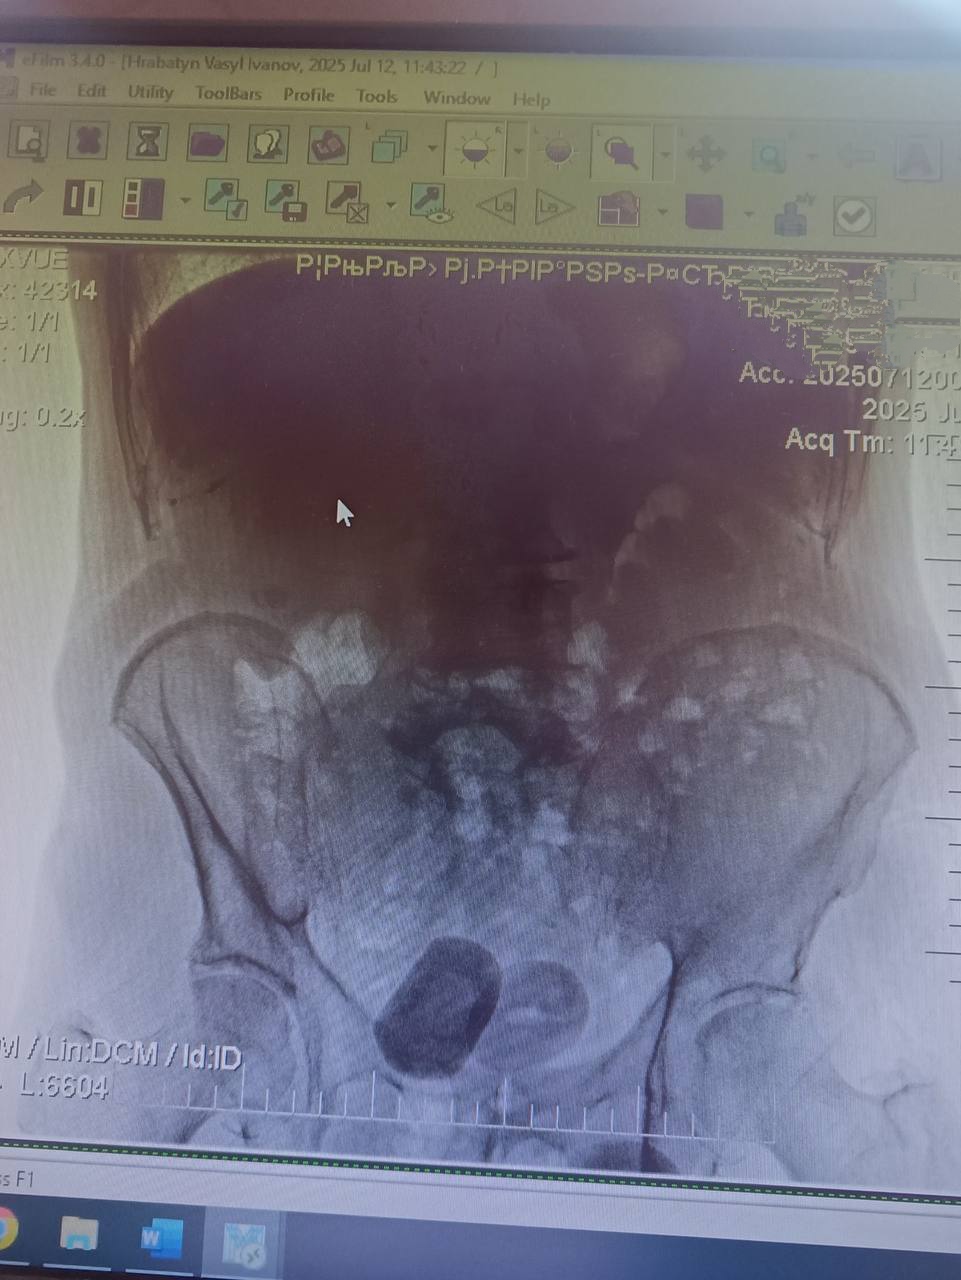

До урологів Центральної міської клінічної лікарні звернувся 76-річний мешканець Івано-Франківська зі скаргами на кров у сечі. Під час обстеження — УЗД та оглядової урографії — медики виявили два великі конкременти в сечовому міхурі, кожен розміром близько 4 см.

Через значні розміри каменів лікарі провели відкрите оперативне втручання — цистолітотомію. Операція виконувалася під спінальною анестезією через розріз над лобком.